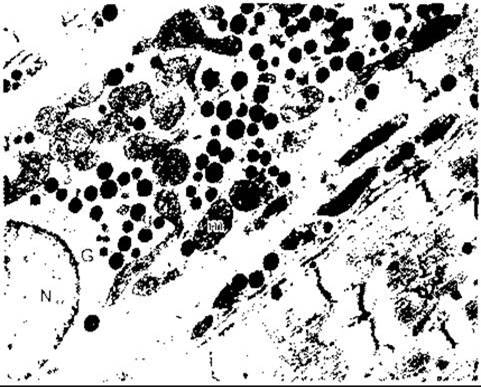

визнана лише недавно. Два з них секретує Серце. М’язові клітини в передсердях і менше у шлуночках містять секреторні гранули (рис. 24-6), кількість яких збільшується зі збільшенням приймання натрію хлориду й об’єму позаклітинної рідини. Екстракти Тканини передсердя здатні посилювати виділення натрію з сечею.

Рис.24-6. Ґранули ANP (д), розсіяні між мітохондріями (т) щура в м’язових клітинах передсердя; G - апарат Ґольджі; N - Ядро. Ґранули у клітинах передсердь людини мають подібний вигляд. х17 640 (з дозволу М Cartin).